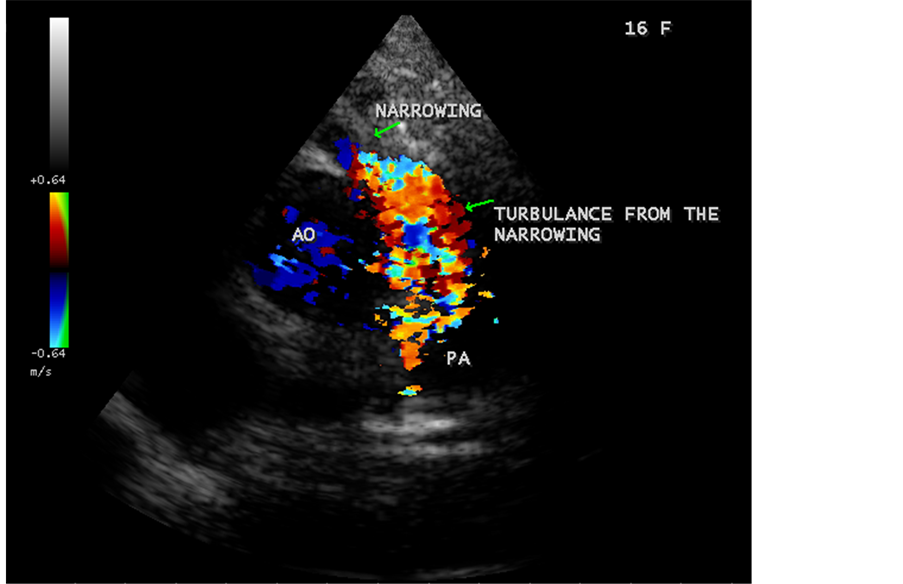

Figure 50. RV EMF in a 16-year-old female―associated with RVOT (RV outflow tract) disease― DCRV (double-chambered RV) as shown in Figure 51, Figure 52 and Figure 53.

Figure 53. Showing the turbulence of flow originating from the muscular narrowing in a 16- year-old female in DCRV.

A left ventricular EMF mimicking apical left ventricular hypertrophic cardiomyopathy as shown in Figure 23, Figure 24 and Figure 25 in a 2-year-old male child and an apical right ventricular hypertrophic cardiomyopathy in a 60-year-old female as shown in Figure 26 mimicking as right ventricular EMF had been found by Transthoracic echocardiographic screening. A right ventricular EMF associated with Psoriasis was shown in Figure 3 to Figure 7 in a 52-year-old male and a left ventricular EMF associated with pemphigus skin lesion in a 63-year-old male as in Figure 40 were detected in this region of Thoothukudi. RV EMF associated with congenital heart diseases such as ostium secundum atrial septal defect in a 26-year-old female antenatally (Primi with 9 months amenorrhea) as shown in Figure 49 and Figure 64 to Figure 66 in a 9-year- old girl. RV EMF associated with RV outflow tract disease (“Double chambered right

ventricle”) in a 16-year-old female as shown in Figure 50 to Figure 53 were detected. RV EMF with rheumatic involvement of mitral valve as shown in Figure 54 and Figure 55 in a 44-year-old female and in Figure 63 in a 55-year old female. Biatrial enlargement due to rheumatic atrioventricular (AV) valves (mitral and tricuspid) involvement characterized by stenosis of the valves are illustrated in Figure 56 to Figure 59 in a 54-year-old female and it is differentiated from EMF which is characterized by AV valve regurgitation as shown in Figure 34 and Figure 60. RV EMF associated with thickening and fibrosis of moderator band in a 16-year-old female was shown in Figure 46. RV EMF associated with apical left ventricular hypertrophic cardiomyopathy was shown in a 47-year-old male as in Figure 61 and in a 65-year-old female as in Figure 62.